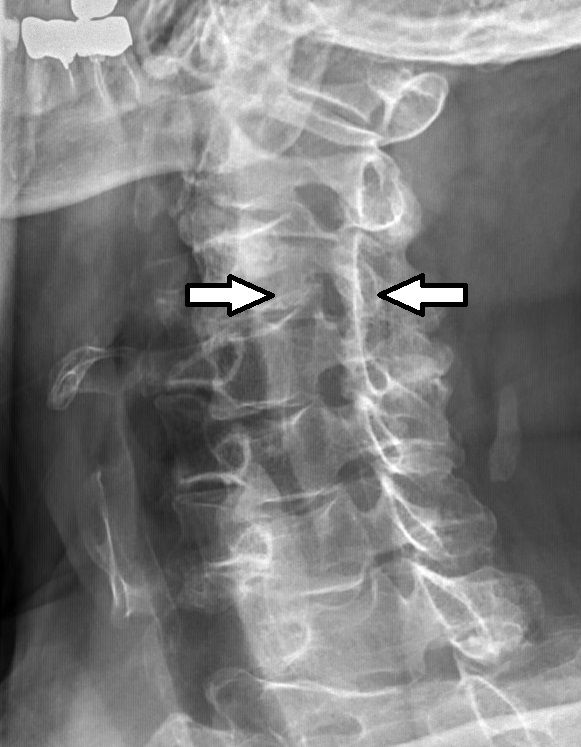

신경근병증은 일반적으로 신경근이 출구 추간공이나 가쪽 함요에서 기계적으로 압박되어 발생한다. 이는 추간판 탈출증(가장 흔하게는 C7, 그 다음은 C6 레벨), 퇴행성 디스크 질환, 골관절염, 후관절 변성/비대, 인대 비대, 척추전방전위증 또는 이러한 요인들의 조합으로 인해 발생할 수 있다.[3][4] 환자에게서 관찰되는 신경근병증의 경우 대개가 C6-C8 지점에 가까운 경추에 위치한다.[29]

보존적 치료 4~6주 후에도 증상이 호전되지 않거나 환자가 50세 이상인 경우 추가 검사가 권장된다.[3] 미국 방사선 학회는 만성 목 통증이 있는 모든 환자에게 투사 방사선 촬영술이 가장 적절한 초기 검사라고 권장한다.[13] 유용할 수 있는 두 가지 추가 진단 검사는 자기 공명 영상과 전기 진단 검사이다. 신경근병증이 의심되는 척추 부위의 자기 공명 영상 (MRI)은 환자의 증상을 유발하는 퇴행성 변화, 관절염 질환 또는 기타 설명 가능한 병변의 증거를 나타낼 수 있다. NCS (신경 전도 검사)와 EMG (근전도 검사)로 구성된 전기 진단 검사는 의심되는 부위에서 신경근 손상을 보여줄 수 있는 강력한 진단 도구이다. 신경 전도 검사에서 복합 근육 활동 전위 감소 및 정상 감각 신경 활동 전위 패턴은 병변이 후근 신경절에 근접해 있을 때 나타날 수 있다. 바늘 EMG는 더 민감한 검사 부분이며, 관련된 신경근의 분포에서 활성 탈신경을 나타낼 수 있으며, 만성 신경근병증에서는 신경성으로 보이는 자발적 운동 단위가 나타날 수 있다. 급성 및 만성 신경근병증 진단에서 전기 진단 검사의 핵심적인 역할을 고려하여, 미국 신경근 및 전기 진단 의학회는 경추 및 요천추 신경근병증 진단에 대한 증거 기반 진료 지침을 발표했다.[14][15] 미국 신경근 및 전기 진단 의학회는 또한 현명한 선택 캠페인에 참여했으며, 이들의 권고 중 일부는 목과 허리 통증에 불필요한 검사와 관련이 있다.[16]